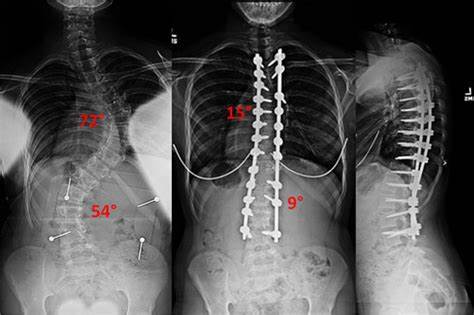

Doppelte Skoliose-Kurve: Diagnose, Behandlungsmöglichkeiten und Management

Die doppelte Skoliosekrümmung bezieht sich auf einen Zustand, bei dem sich die Wirbelsäule in zwei verschiedene Richtungen krümmt. [...]